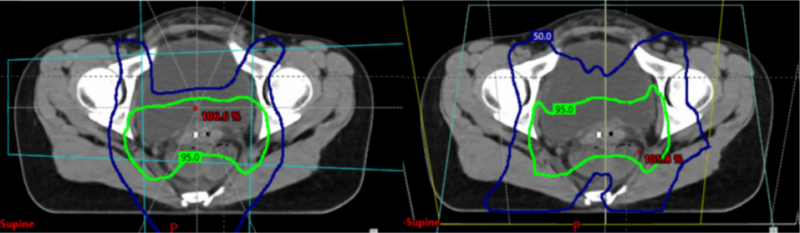

有一项纳入10例患者的剂量学研究,比较了调强放疗、被动散射和笔形束扫描(PBS)。在研究中,与调强放疗相比,使用任何一种质子治疗技术都可减少小肠、肾脏和脊髓的高剂量和低剂量放射暴露(图1)。PBS质子治疗可减少盆腔骨髓、小肠和大肠在放射治疗中的暴露,降低小肠、膀胱和直肠的平均剂量,还可减少卵巢的暴露,保留内分泌功能和防止过早绝经。但质子治疗时,肠道气体、身体状态变化、内部器官运动和硬件植入(如髋关节置换)等因素增加了腹腔、盆腔器官治疗的不确定性。此外,缺乏高质量的成像限制了质子治疗的广泛应用。

图1.质子治疗(左)与调强放疗(右)。95%的处方剂量(绿色)表明两种方案中阴道和淋巴结周围的适形性相当。50%处方剂量线(蓝色)显示质子治疗对正常器官的剂量低于调强放疗。